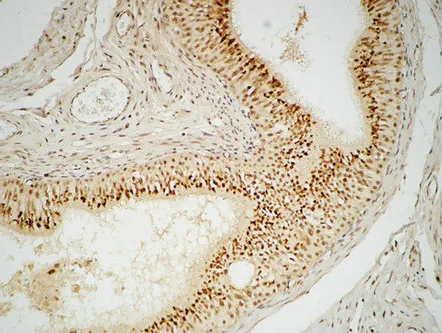

Sox-9 Rabbit Polyclonal Antibody

Cat: APRab18144

Size1:50μl Price1:$118

Size2:100μl Price2:$220

Size3:500μl Price3:$980

Size2:100μl Price2:$220

Size3:500μl Price3:$980